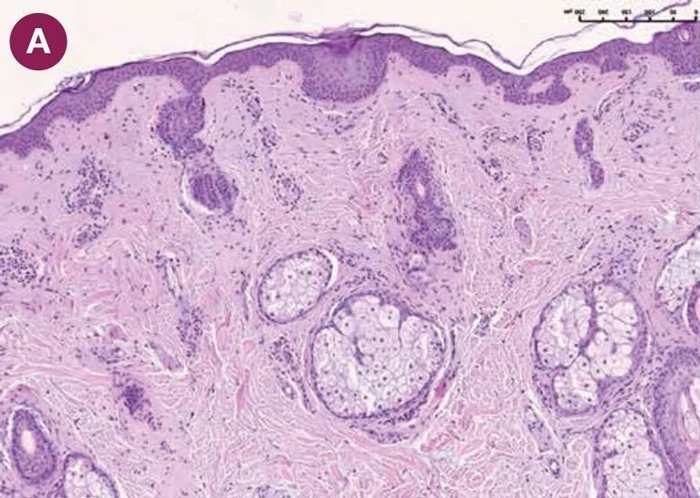

После применения нативной ГК (Hyon 1,8 %) наблюдались выраженные структурные изменения. В микросрезах отмечено утолщение эпидермиса, преимущественно за счет шиповатого слоя, увеличение толщины сосочкового слоя дермы (рис. 3 А, B). В сосочковом слое было отмечено повышение плотности клеточных элементов. В сетчатом слое визуализировались крупные пучки коллагеновых волокон (рис. 3 C, D).

увеличение толщины сосочкового слоя дермы

крупные пучки коллагеновых волокон

После применения нативной ГК морфологические изменения сосочкового и сетчатого слоя дермы могут быть обусловлены созданием благоприятной для синтеза среды для фибробластов (с повышением сигналинга), а изменения эпидермиса — улучшением кровоснабжения дермы и доставки питательных веществ к эпидермису через дермо-эпидермальную границу.